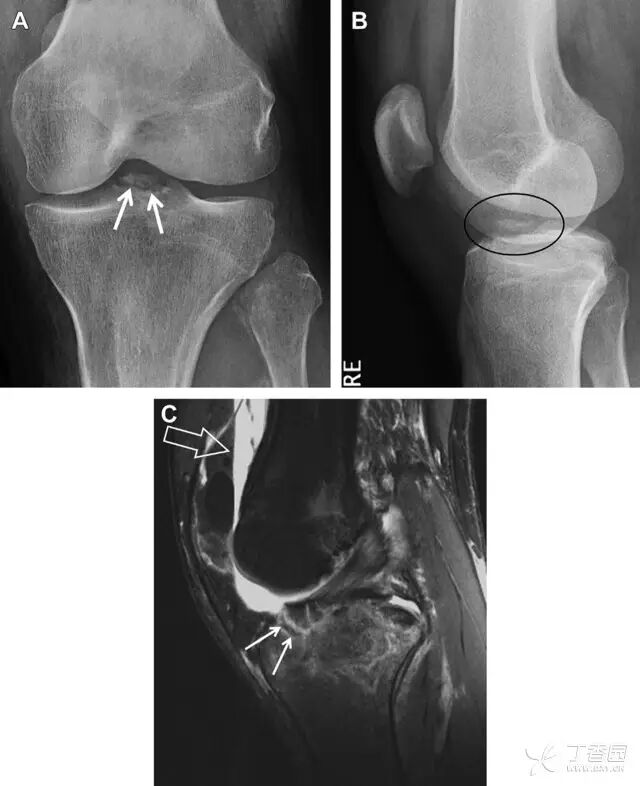

前交叉韧带撕脱骨折常发生在胫骨髁间嵴(图 1)。这种骨折在青少年中常见,但在成年人中也并不像大家想象的那么少见。

图 1 摩托车事故患者前交叉韧带撕脱性骨折

A 正位片示胫骨髁间嵴底部骨折(箭头),注意别把这个骨折碎片错认为关节内结构。B 侧位片示胫骨上方可见一细长型骨折碎片(椭圆)。C MRI 矢状位 T2 加权像示前交叉韧带附着于撕脱的骨折碎片上(箭头),注意周围存在骨髓水肿和积脂血征(空箭头)。

图 2 扭伤后的股骨外侧髁凹陷征

A 侧位片示股骨外侧髁凹陷。B MRI 矢状位 T2 加权像示股骨外侧髁及胫骨后外侧骨挫伤(空箭头)。胫骨近端随着后交叉韧带撕裂发生移位,露出外侧半月板的后角(弧形箭头)。